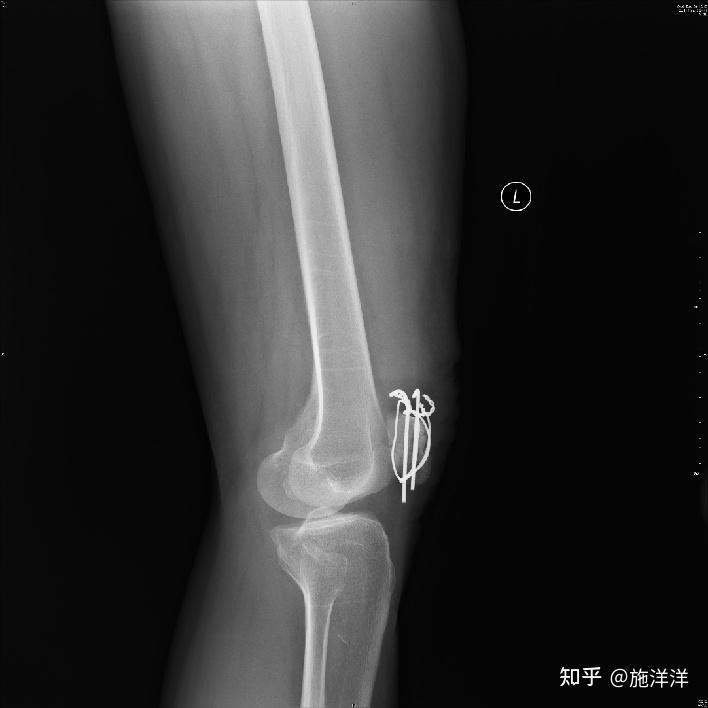

髕骨骨折-占全身骨折的1%-關(guān)節(jié)囊內(nèi)骨折-可造成髕股關(guān)節(jié)及脛股關(guān)節(jié)的嚴(yán)重?cái)伩s與粘連-髕骨是股四頭肌肌腱中的籽骨-髕骨是重要的伸膝裝置-損傷后股四頭肌可發(fā)生明顯的抑制與萎縮髕內(nèi)側(cè)支持帶(MedialRetinaculum)髕外側(cè)支持帶(LateralRetinaculum)最后15°的終末端伸膝需要的力矩是從完全屈膝到伸膝15°需要的力矩的2倍,髕骨能夠很好的為伸膝動(dòng)作提供力矩,而髕骨骨折患者就容易出現(xiàn)伸膝滯后的現(xiàn)象,在伸膝最后15°膝控變差。髕骨增加了股四頭肌的杠桿臂,增加了伸肌力量的30%。髕股關(guān)節(jié)壓力髕股關(guān)節(jié)壓力站立屈膝30°=體重站立屈膝60°=體重×4站立屈膝90°=體重×6平地行走時(shí)=體重×0.6平地快速行走=體重×1.5上下樓梯=體重×3.3下蹲站起=體重×8從完全屈曲到伸直髕骨大約移動(dòng)7cm,在整個(gè)rom中,只有13-38%的髕骨關(guān)節(jié)面與股骨接觸。髕股間接觸區(qū)屈膝時(shí)隨屈曲運(yùn)動(dòng)髕骨接觸面上移,同時(shí)接觸面積增加。膝伸直時(shí),髕骨下方與股骨髕面接觸,屈曲至90度時(shí)則接觸區(qū)移到髕骨上部和髁間窩。損傷機(jī)制&骨折分型直接暴力間接暴力內(nèi)固定類(lèi)型“8”字張力帶鋼絲張力帶對(duì)于術(shù)后康復(fù)的重要意義拉應(yīng)力轉(zhuǎn)化為壓應(yīng)力從而有利于骨折愈合,因此非負(fù)重狀態(tài)下的股四頭肌力量訓(xùn)練有助于骨折愈合然骨折未愈合前,內(nèi)固定承擔(dān)了遠(yuǎn)遠(yuǎn)高于體重的壓力,過(guò)早進(jìn)行肌力訓(xùn)練有發(fā)生內(nèi)固定斷裂的危險(xiǎn)術(shù)后1-7天常規(guī)術(shù)后患肢抬高、持續(xù)冷療、TENS鎮(zhèn)痛、踝泵股四頭肌力量訓(xùn)練等長(zhǎng)收縮(輕柔)直腿抬高SLR(內(nèi)固定牢固)早期ROM訓(xùn)練根據(jù)術(shù)中情況決定安全角度(術(shù)中記錄屈膝到多少度骨折斷端依然穩(wěn)定-如90°)主動(dòng)屈膝被動(dòng)伸膝借住扶柺或助行器,直腿支具保護(hù)下(3-4w)可耐受的負(fù)重行走2-6周髕骨滑動(dòng)-輕柔NMES肌肉再教育5-6周可開(kāi)始無(wú)阻力的功率自行車(chē),座位抬高6w后X-Ray驗(yàn)證骨折愈合情況閉鏈訓(xùn)練微蹲mini-squats臺(tái)階(臺(tái)階高度4-inch,約10cm)PT凳滑行stoolscoots腘繩肌力量訓(xùn)練-負(fù)重屈小腿增加功率自行車(chē)訓(xùn)練量并發(fā)癥膝關(guān)節(jié)僵硬:最常見(jiàn)的并發(fā)癥感染:少見(jiàn)內(nèi)固定松動(dòng)、斷裂Upto20%創(chuàng)傷性骨關(guān)節(jié)炎:骨不連<1%內(nèi)固定造成的疼痛:約15%因此去除內(nèi)固定